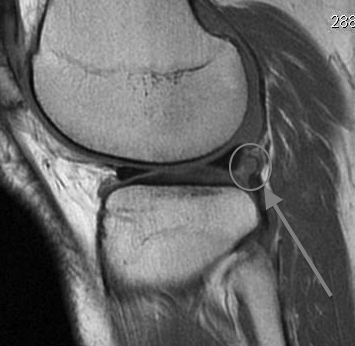

MRI

Loose body in posterolateral compartment